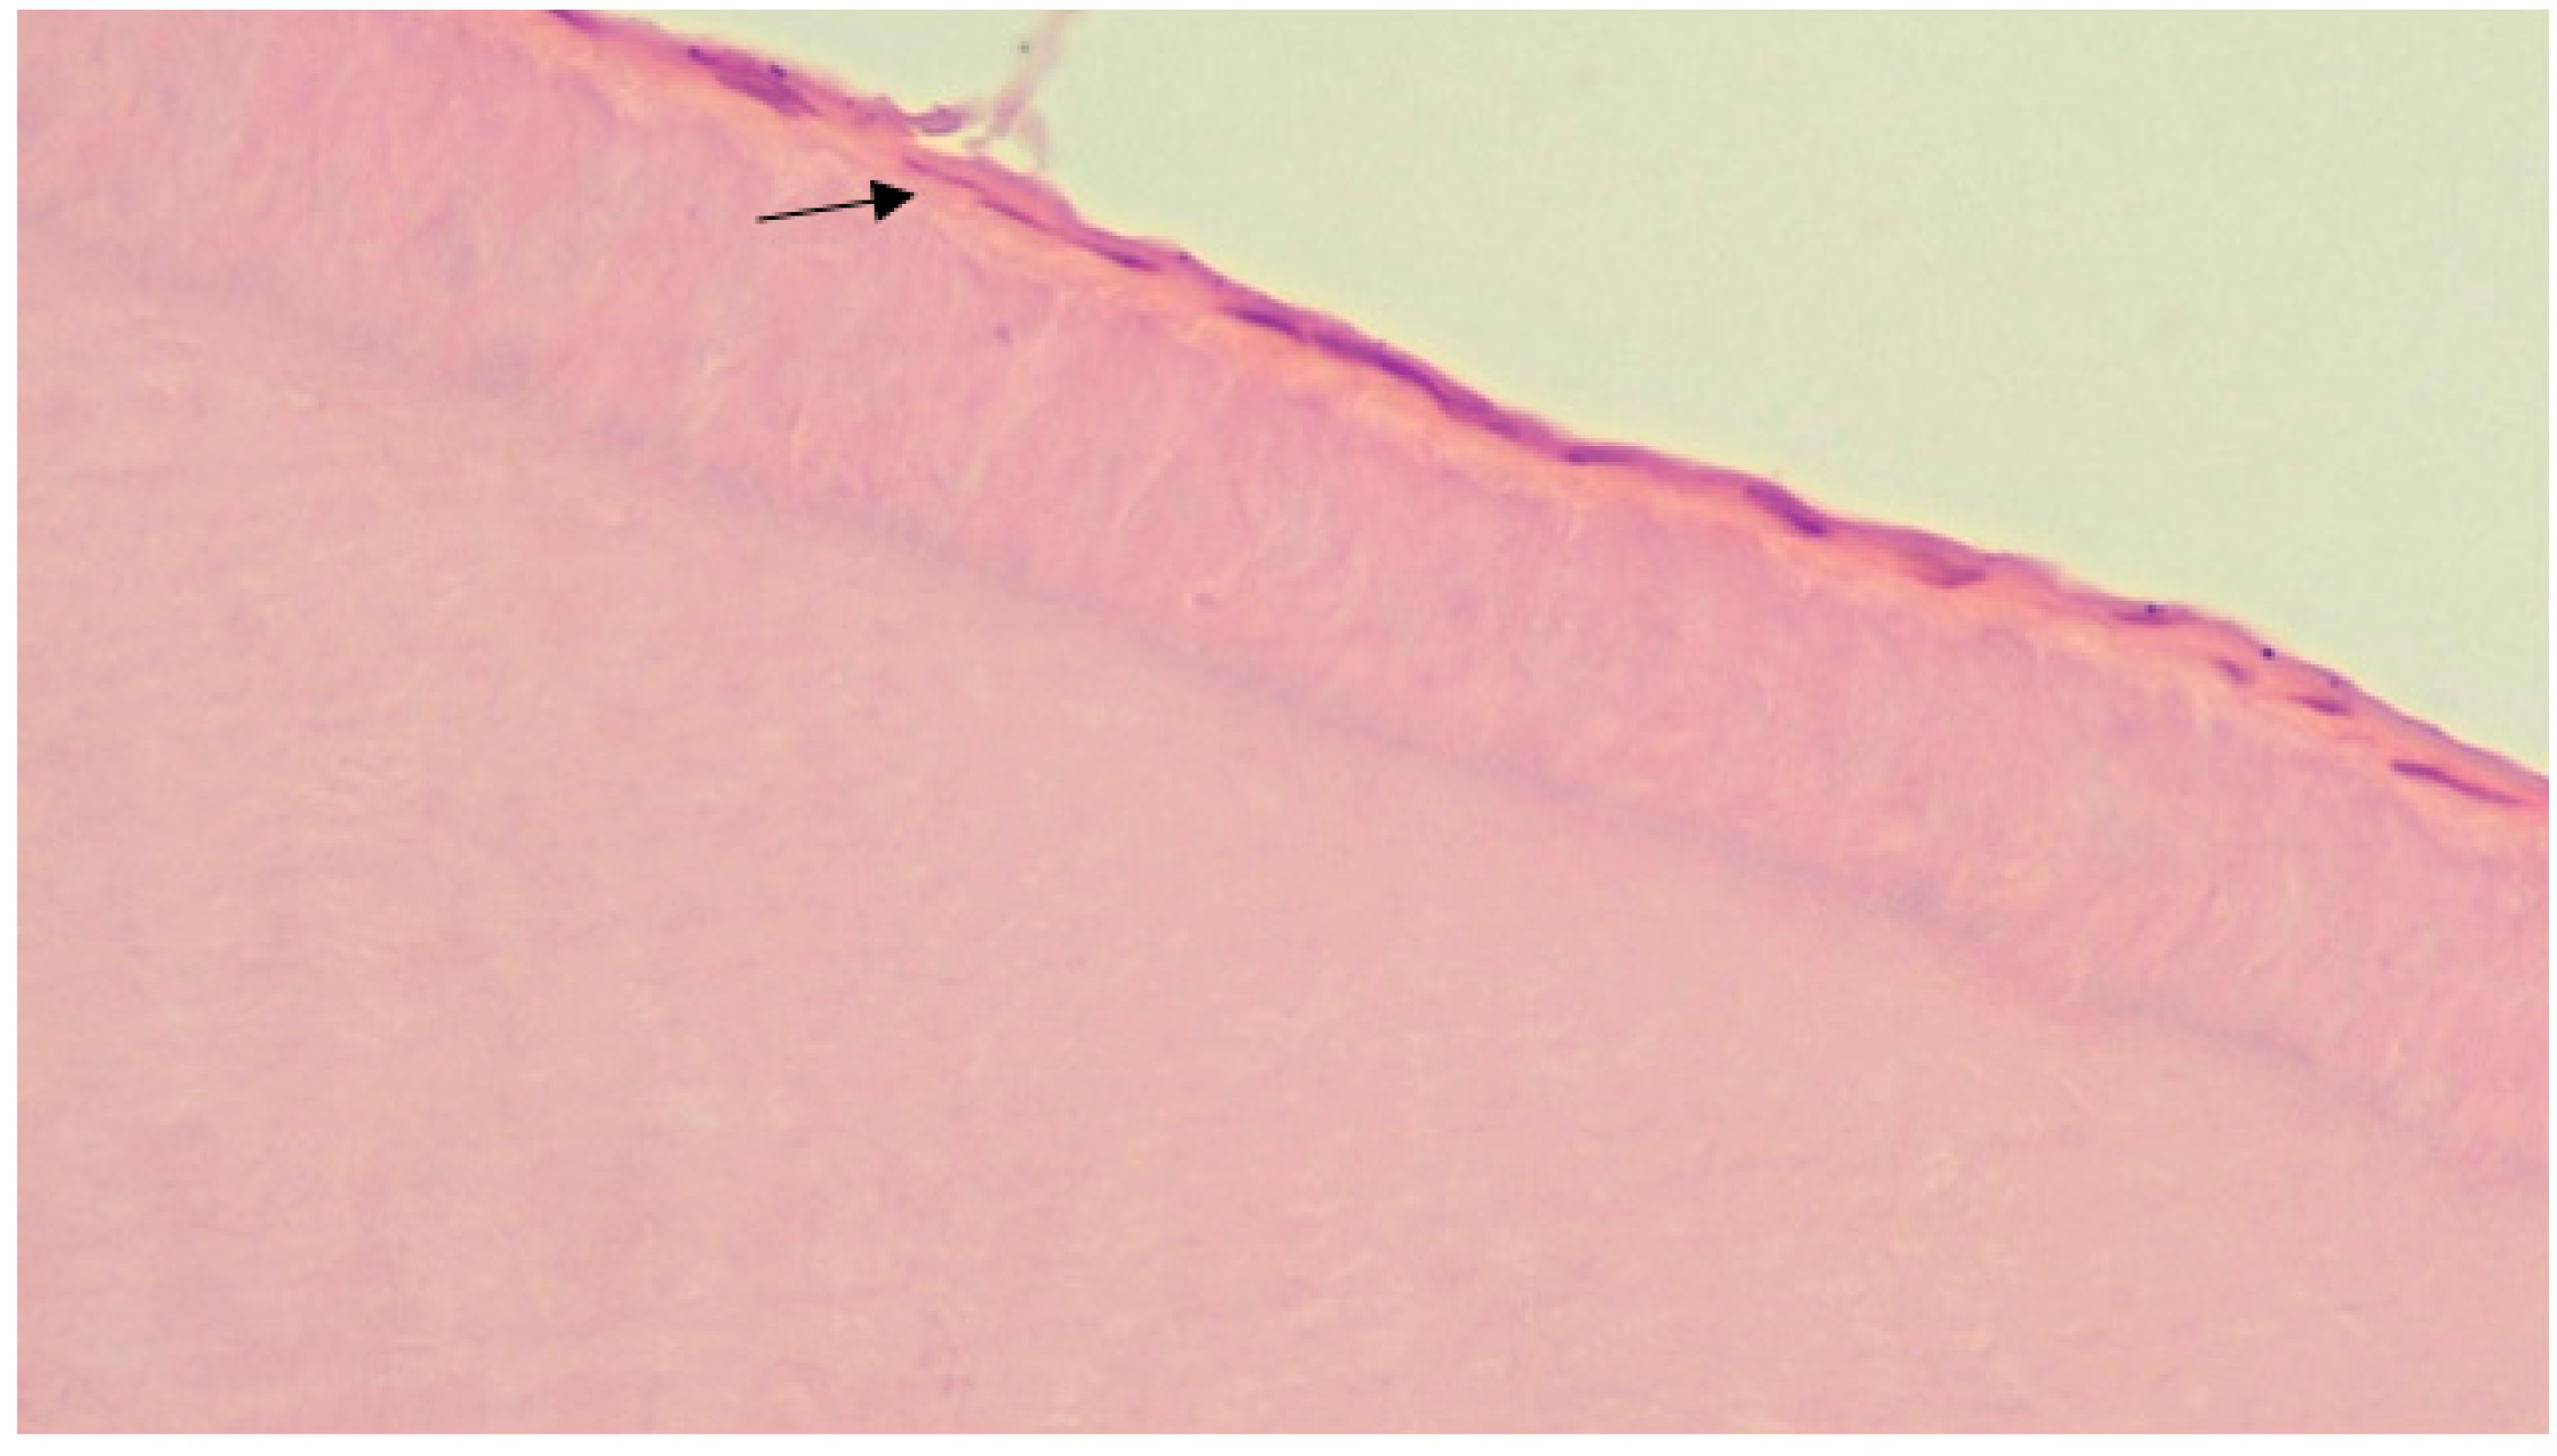

3.2. Results of Morphological Study